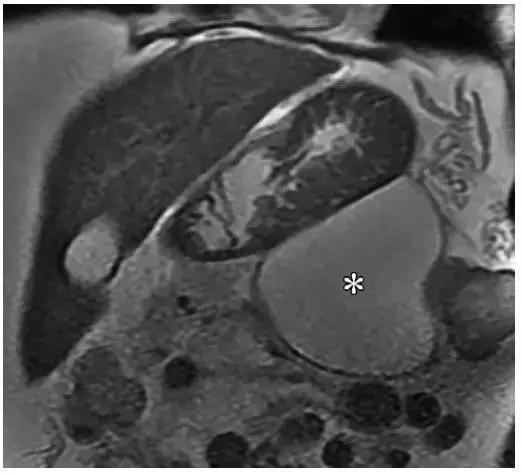

在 MR 成像中,假性囊肿表现为均匀高 T2 信号(图 6)。MRCP 具有高组织分辨率,可以显示部分假性囊肿与胰管相通(图 7)。

低于 10% 的 IEP 患者的假性囊肿会进展。典型假性囊肿位于胰周,极少数情况下,坏死组织清除术后胰管内胰液流入手术部位形成胰腺内假性囊肿。

在这些病例中,坏死组织清除术后或胰体坏死,而胰尾仍有功能,分泌胰液并从胰管内漏出形成假性囊肿(图 7)。